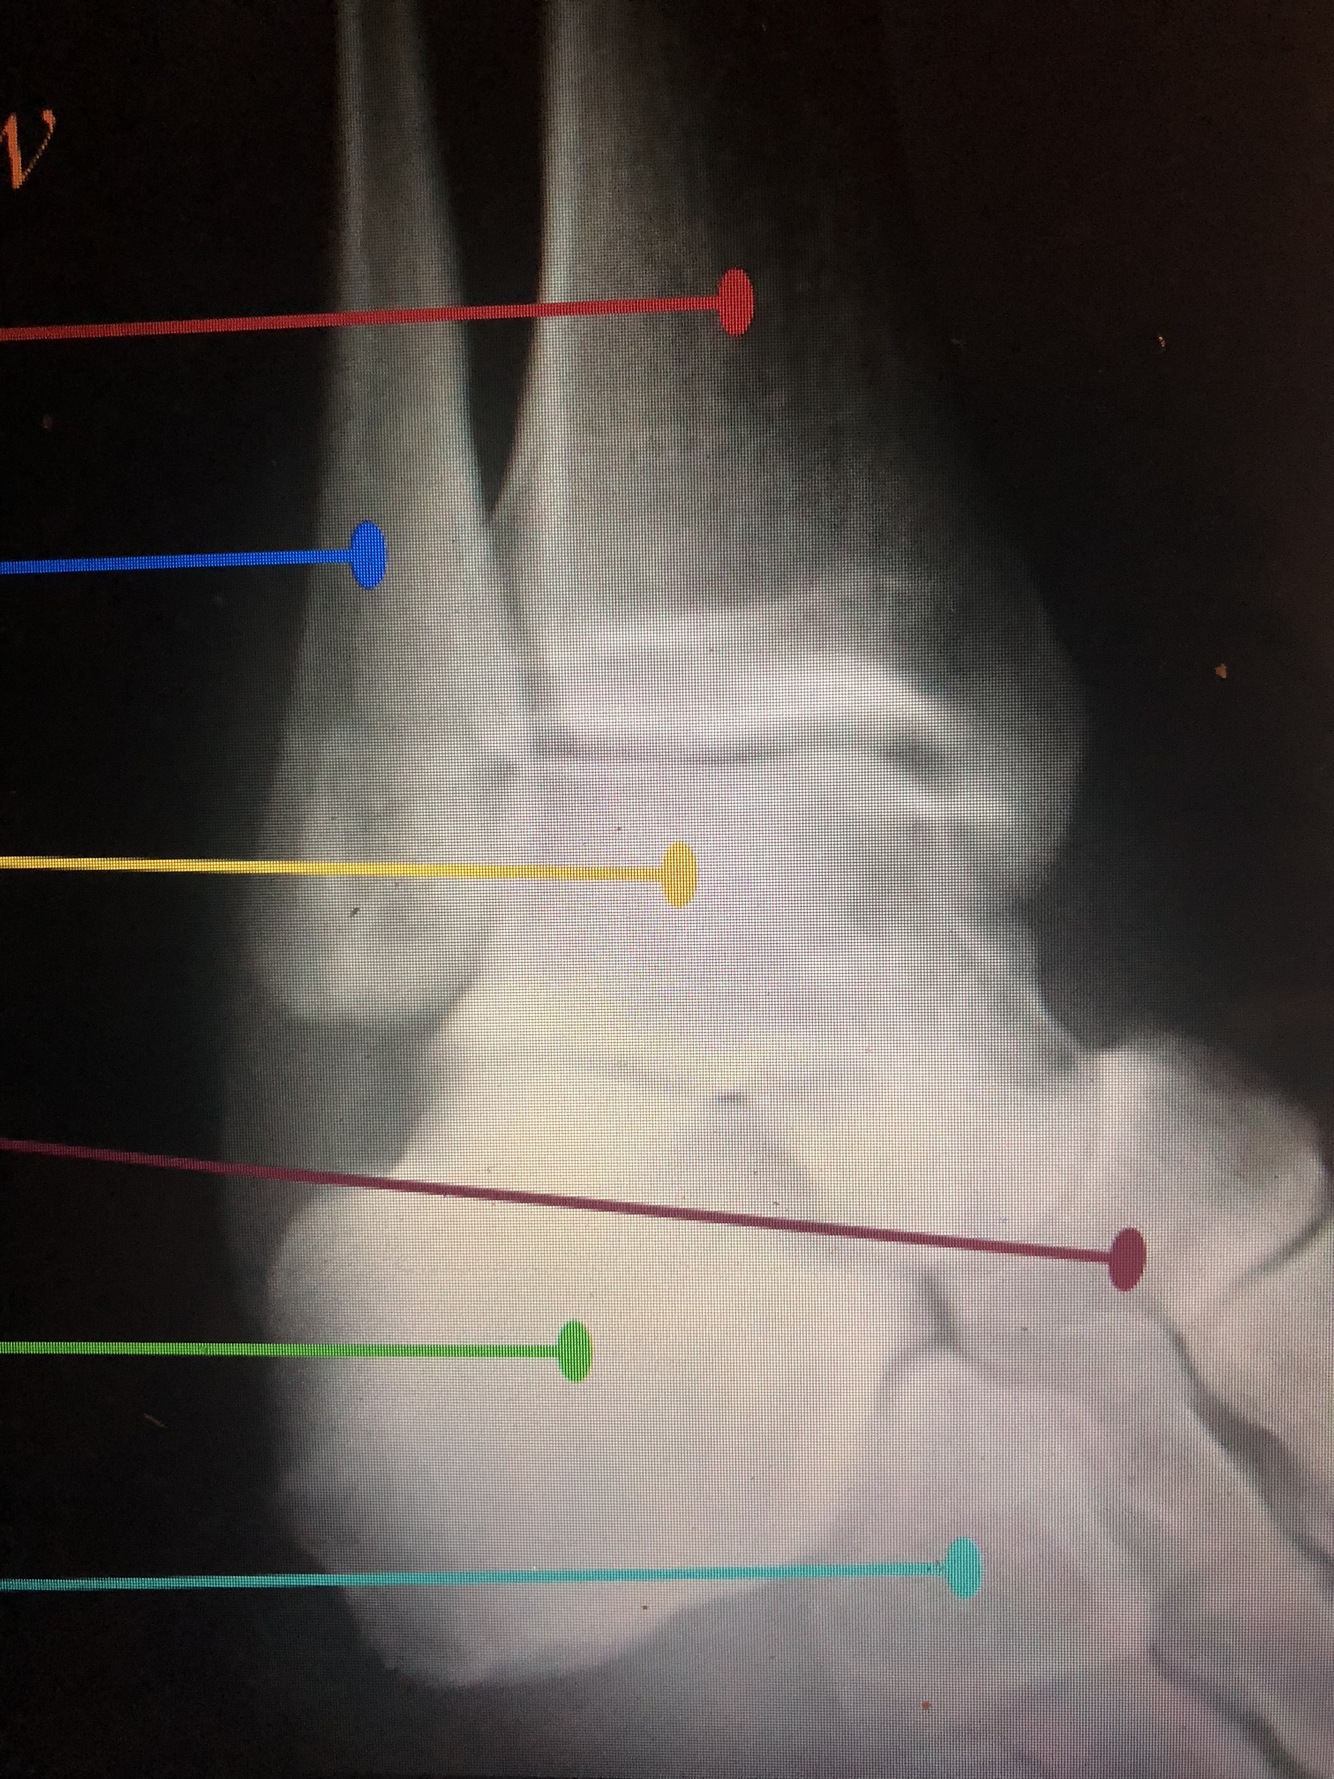

What is the dark blue line?

Lateral margin of the Tibia

What is the red line?

Plafond

What is the light blue line?

Medial Malleolus

Interosseous Crest of the distal tibia

What is the light blue dotted line?

Fibular Notch

What is the red dotted line?

Posterior Malleolus